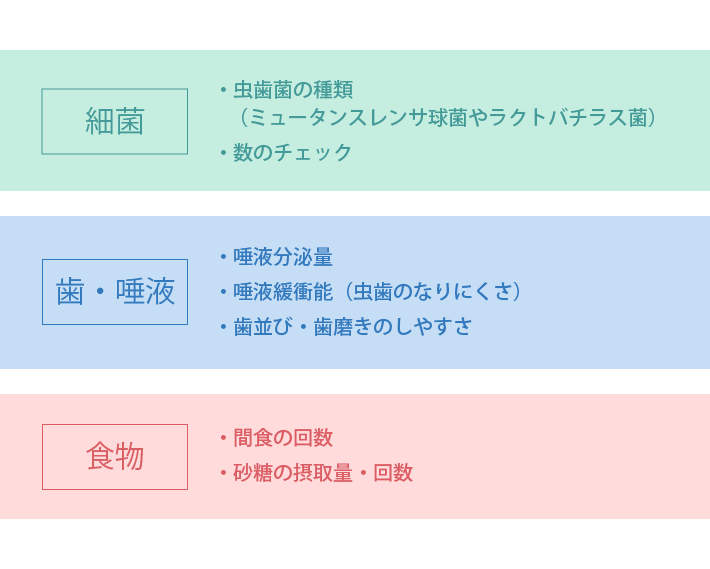

虫歯リスク検査(SMT唾液検査)

虫歯になる将来予測をすることです。虫歯は細菌による感染症で、その感染リスクは人によってさまざまです。

征矢歯科医院で行なっている虫歯リスク検査は5分で虫歯菌数、唾液の量や性質、生活環境の中に潜むリスク因子などを詳しく調べることができます。患者様が無理なく続けられる一人ひとりに合った治療プランや予防プログラムをご提案します。

虫歯の原因はプラーク中の細菌ですので、虫歯予防には歯磨きが大切です。しかし、ほとんど歯磨きをしないのに虫歯が一本もない人、一生懸命歯磨きをしているのに虫歯ができてしまう人もいます。この違いは一体どこにあるのでしょうか? 虫歯に罹患するかどうかの重要因子には細菌・食物(糖類)・歯と唾液があります。